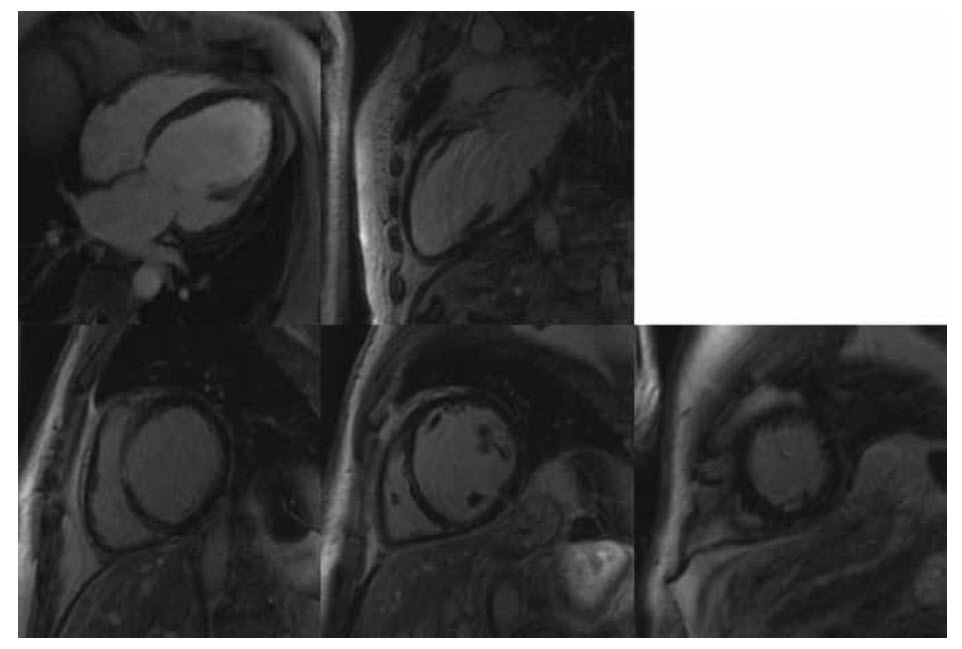

A 65-year-old man presents with angina to the outpatient clinic. There is a past history of myocardial infarction 10 years earlier. You list him to have an angiogram. The angiogram demonstrates an occluded left anterior descending artery and a 90% stenosis of the right coronary artery. A CMR is requested to assess viability prior to any potential intervention.  Video below shows the CMR long axis cines

Video below shows the short axis cines.

The late myocardial enhancement is shown below

Which of the following statements is correct?

A. The LAD territory is non-viable

B. The entire lateral wall is infarcted

C. The RCA territory is non-viable

D. Both LAD and RCA territories show >50% wall-thickness infarction

E. There is right ventricular infarction